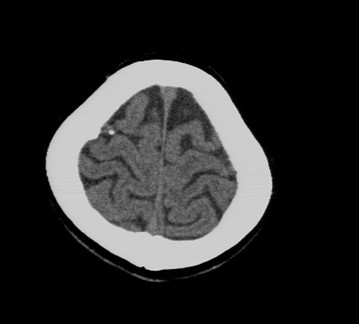

后枕部疼痛来检查的,无任何相关病史

骨瘤吧?

考虑脑膜钙化或小脑膜瘤钙化。

钙化

考虑骨瘤或小脑膜瘤钙化。

脑沟内钙化灶,考虑陈旧性脑膜感染

钙化灶。

钙化灶

考虑脑膜钙化

小脑膜瘤钙化

良性钙斑

考虑脑膜钙化或小脑膜瘤钙化